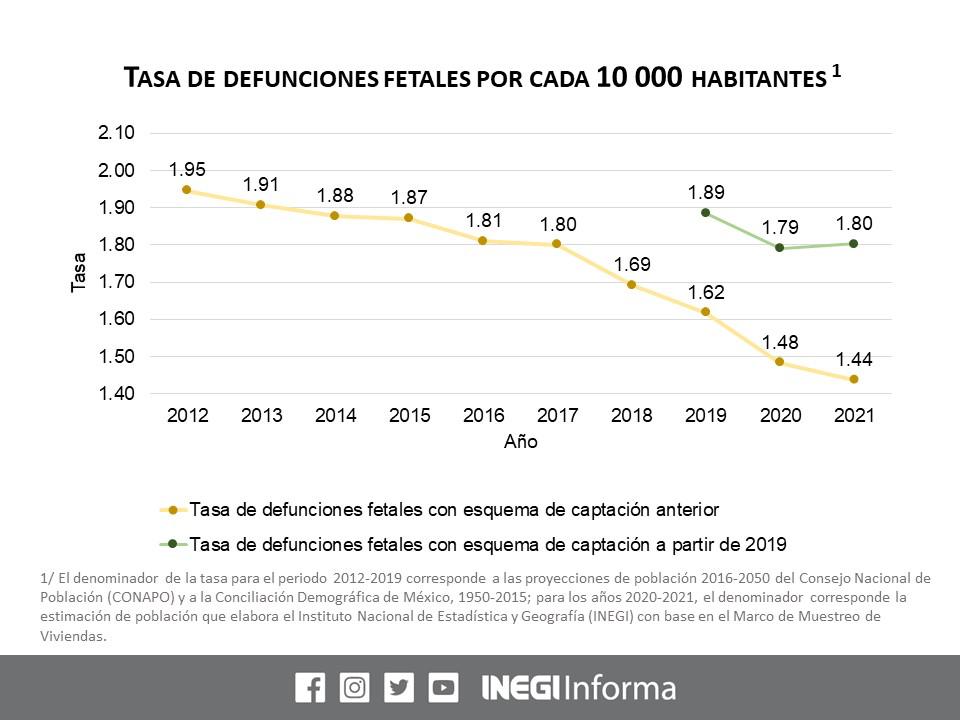

El Inegi dio a conocer que durante 2021 se registraron 23 mil muertes fetales, una tasa de 1.80 habitantes por cada 10 mil

Después de un descenso en 2020 durante 2021 repuntaron las muertes fetales en México.

El Instituto Nacional de Estadística y Geografía (Inegi) dio a conocer que durante 2021 se registraron 23 mil muertes fetales, una tasa de 1.80 habitantes por cada 10 mil, lo que representa una décima más que el año anterior.